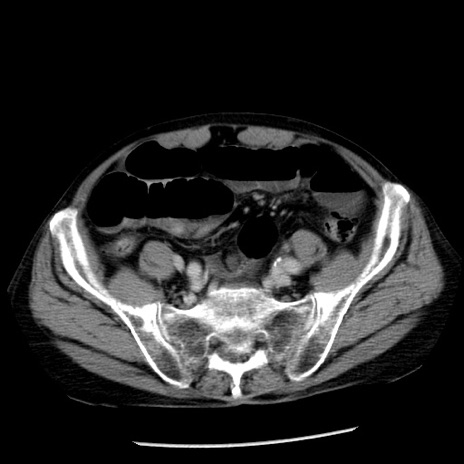

症例26(横断像)

【症例】80歳代男性

【主訴】嘔吐

【現病歴】昨晩2回嘔吐あり、今朝になっても嘔吐あり。来院。

【既往歴】胃潰瘍

【身体所見】意識清明、BT 37.6℃、BP 166/95mmHg、HR 100bpm、SpO2 97%、腹部:平坦・軟、腸蠕動音聴取良好、圧痛なし。

【データ】WBC 21900、CRP 1.46